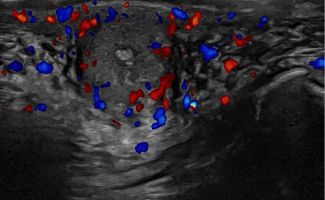

Πολλές αλλοιώσεις και παθήσεις μπορούν να απεικονιστούν υπερηχογραφικά και να μελετηθούν αξιόπιστα με τη βοήθεια του Έγχρωμου Doppler και της Ελαστογραφίας .

- Αιμαγγειώματα, αγγειοδυσπλασίες (αγγειακού τύπου βλάβες)